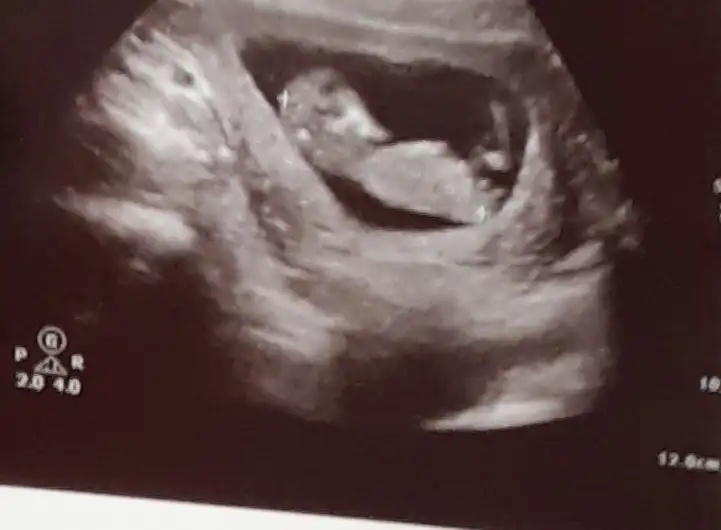

12+4..tahmininizi bekliyorum..

Eklentiler

• 20201022_181417.webp

20201022_181417.webp

32,1 KB · Görüntüleme: 91

• 20201023_150518.webp

20201023_150518.webp

34,4 KB · Görüntüleme: 80

• 20201023_150459.webp

20201023_150459.webp

40,8 KB · Görüntüleme: 79

Doktor erkek dedi ama 12.hafta olunca ben emin olamadım. Pipi fotosu da vermiş, ona da bakınca çok emin olamıyorum. Belli bir aya dek benzer gittiği için genital organlar, belki yanılmıştır diyorum..kız istediğim için..umarım bir ay sonra, yanılmışım, kızmış der doktor..